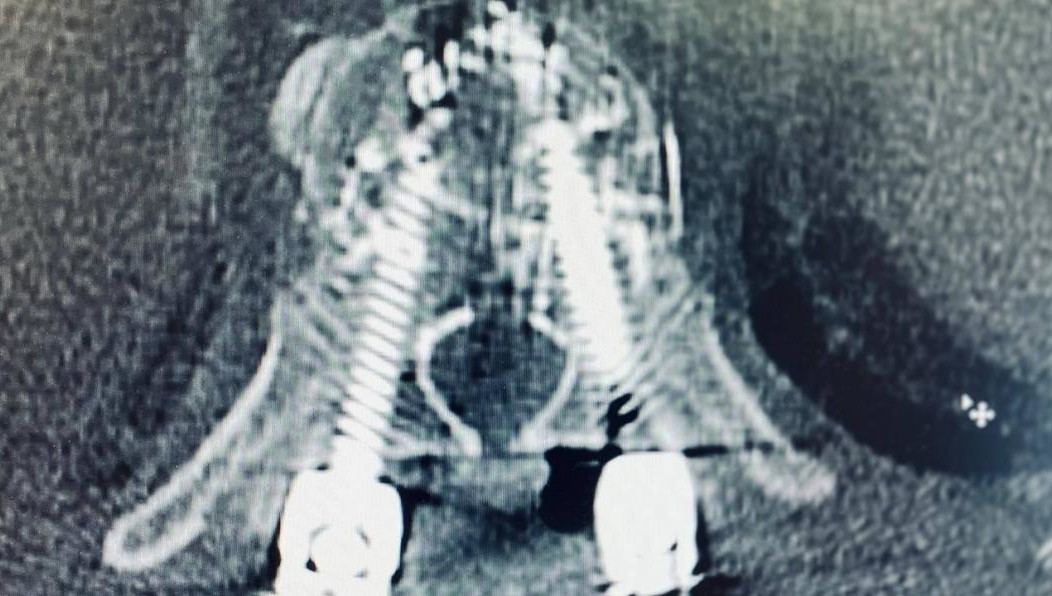

Год назад мужчина получил компрессионный перелом. Из-за остеопороза у него деформировались позвонки, они начали вызывать нестерпимую боль. В лечении врачи применили технику транспедикулярной фиксации под рентген-контролем методикой free hand. Они установили восемь винтов из титана в позвоночник, скрепив конструкцию специальным цементом для костей.

— При установке фенистрированных винтов нет права на ошибку. Нужно четко попасть в тело позвонка через ножку, сохранив все стенки, чтобы цемент не попал в позвоночный канал и близлежащие сосуды, — рассказал нейрохирург Ильфат Фатхутдинов.